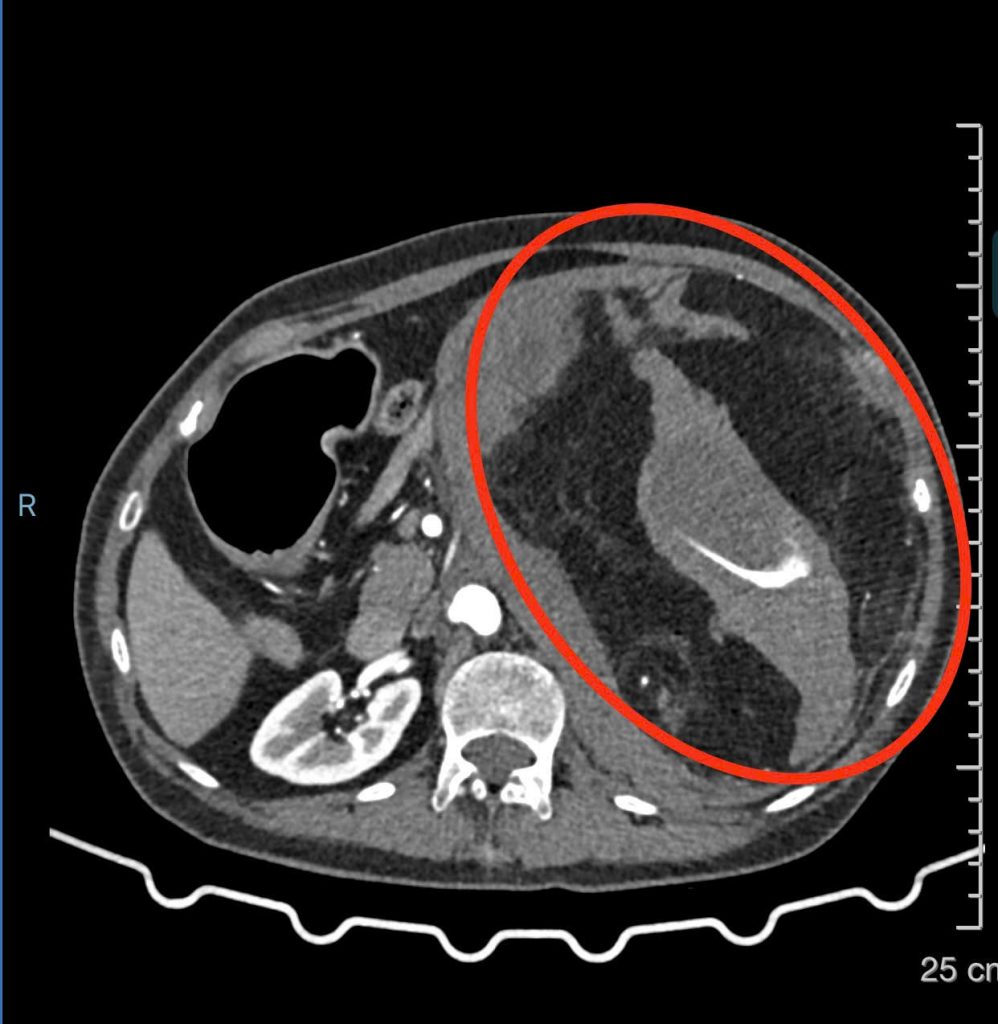

Hình ảnh CT scan

Hình ảnh CT scan khối bướu thận gây xuất huyết